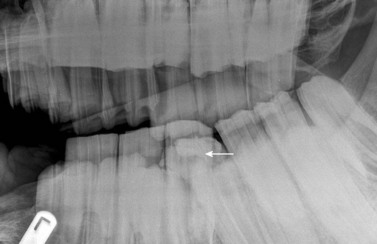

image image image

Fig. 13.36 Polydontia. Supernumerary maxillary cheek teeth (Triadan12s) are the most common supernumerary cheek teeth in horses. The 12 is usually markedly overgrown as in (A) but may be unerupted as in (B) if there is inadequate space (overcrowding). Note the abnormal shape of the apical area of the 112. (C) An example of overgrown bilateral supernumerary mandibular 12s.

Fig. 13.37 (A) Maxillary cheek tooth row of a miniature Shetland pony with marked dysplasia of the 109, 110, and 111 and a corresponding wave mouth on the mandibular row. (B) Markedly enlarged, radiodense, dysplastic 110, which has displaced the reserve crowns and apices of 111 and 109 caudally and rostrally, respectively. (C) Abnormally small 302. The deciduous 702 remnant is retained (arrow).